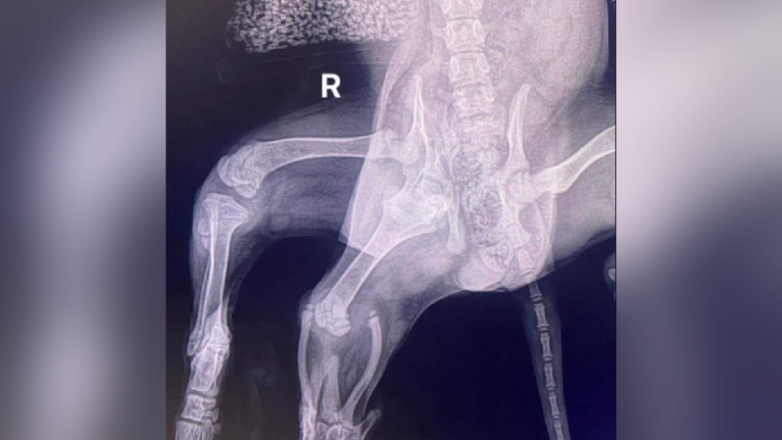

Пожертвования на проведение операции в общей сумме 15 тыс. фунтов для Ариэль собирали буквально всем миром. Ситуация осложнялась тем, что у кокер-спаниеля с одной стороны было два тазобедренных сустава, что не позволило тазу правильно сформироваться. Томография также показала наличие только одной почки.

Рентген показал, что у Ариэль было два тазобедренных сустава с правой стороныИз-за слабого мышечного тонуса нормальной правой задней лапы был риск и её ампутации. Но за последние месяцы она достаточно укрепилась. И этого удалось избежать.